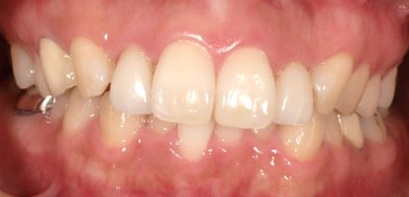

治療前

治療終了前